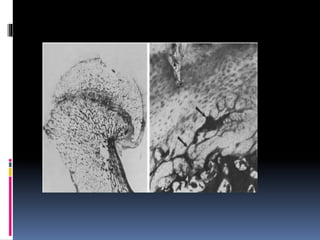

 Physis layers:

1. Germinal layer – zone of resting cartilage cells.

2. Proliferative zone – actively growing cartilage cells.

3. Zone of hypertrophy – chondrocytes become swollen & vacuolated.

4. Zone of calcification – chondrocytes become calcified.